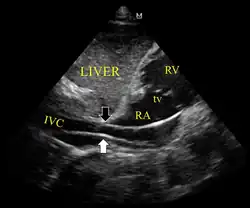

Ultrassonografia mostrando o dispositivo no ventrículo direito

Ultrassonografia mostrando o dispositivo no ventrículo direito -

Dispositivo passando de forma inadequada para a veia cava inferior

Dispositivo passando de forma inadequada para a veia cava inferior -